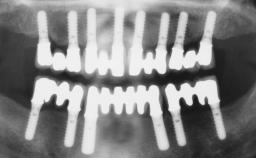

A 56-year-old female patient was referred to the clinic because of retention problems with her mandibular denture. She had been completely edentulous for more than 33 years and wore her sixth set of complete conventional dentures, which had been delivered 5 years previously. An oral surgeon had performed a vestibuloplasty in the interforaminal region of the mandible with a piece of skin tissue 12 years earlier. The panoramic radiograph and lateral cephalometric radiograph exhibited the hypotrophy of the inferior alveolar process. The mandible was a Cawood class VI,and the height of the mandible in the interforaminal zone was 15 mm.